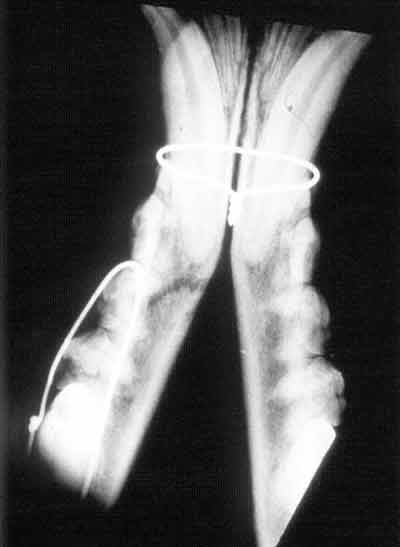

The patient is in dorsal recumbency, with the hard palate parallel

to the film. If possible, the endotracheal tube should be removed

before exposure.

The diagnostic ability of this technique is limited by superimposition

of structures. An intra-oral technique can also be performed with

less superimposition.

Positioning for Ventro-dorsal skull